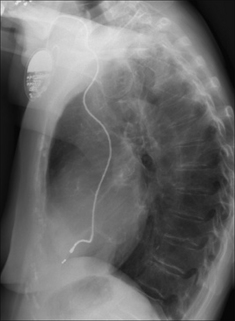

PACEMAKER CHECKLIST—THE LATERAL CXR

1. Ventricular lead:

image The tip should be directed anteriorly and inferiorly (Figs 12.13 and 12.14).

image

Figure 12.13 Normal position of a ventricular lead.